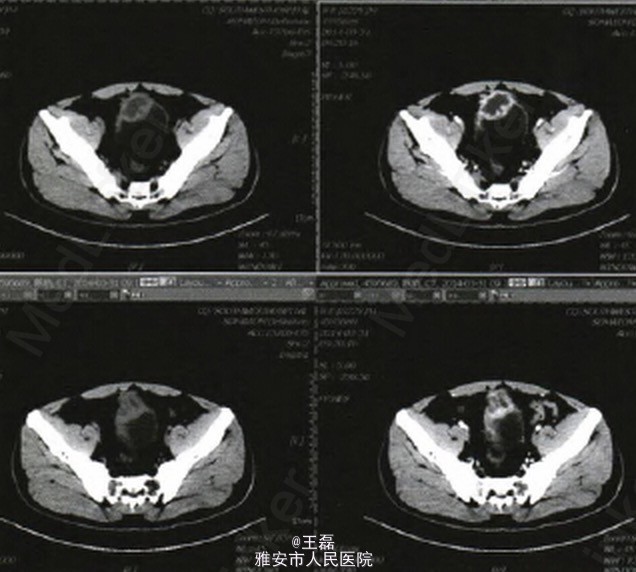

膀胱超声提示:膀胱前壁低回声,性质待定 CT检查提示:膀胱顶部占位;膀胱癌? 门诊膀胱镜检查发现膀胱顶部3 cm×3 cm×3 cm大小类圆形占位,表面滤泡样改变,基底部较广。取病理活检提示:(膀胱顶部)送检少许破碎组织显示尿路上皮增生(送检组织较少)。

该患者CT片表现与脐尿管癌严重感染时CT表现极为相似:膀胱顶部占位,囊壁明显增厚,增强后强化明显,伴腔内脓肿形成。因门诊活检为:(膀胱顶部)送检少许破碎组织显示尿路上皮增生,送检组织较少,加之患者年龄较小,故行麻醉下经尿道膀胱占位活检术,术中活检为慢性膀胱炎,又行膀胱部分切除术,术后病检报告为:(膀胱)慢性肉芽肿性炎伴微脓肿形成。 肉芽肿是一种以肉芽肿形成为主要特征的慢性增生性炎症。一般由细菌、真菌、异物等感染引起。腹腔镜阑尾切除术后并发症中,术后感染、脓肿等并发症发生率极低,因感染至膀胱慢性肉芽肿性国内报道少见。本例患者可能系化脓性阑尾炎细菌感染至盆腔腹膜反折处,反复刺激引起膀胱顶壁与腹膜炎症,瘢痕及纤维化,最终导致(膀胱)慢性肉芽肿性炎伴微脓肿形成。